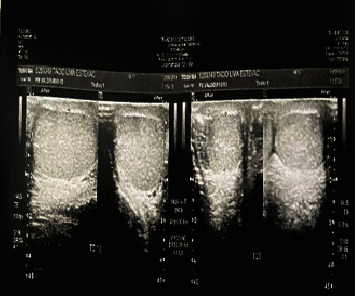

A 17-year-old patient with acute testicular pain had no blood flow observed on scrotal ultrasound Doppler on either side, suggestive of bilateral torsion. The patient underwent immediate scrotal surgical exploration, and a numerical anomaly was observed during surgery-there were two testicles on each side, and all four exhibited torsion. After detorsion, circulation was recovered, and three of four testicles were kept. One dystrophic testis was removed.